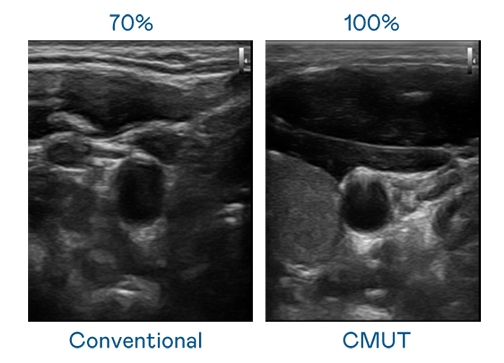

CMUT 技术是一种用电容式微机电元件来产生超音波讯号的技术。与传统 PZT 压电式技术相比,CMUT 频宽增加 30%,更宽频的超音波讯号让影像解析度大幅提升,是实现高影像品质医疗超音波扫描、促进精准医疗发展的关键技术。

超音波影像的解析度高低,首先取决于探头能发出的讯号频宽。九游会 CMUT 可提供高清晰的超音波讯号,提供高频宽、高灵敏度、影像纹理细节更高的超音波影像,协助医护人员缩短影像判读时间及利用精准的医疗影像进行诊断。